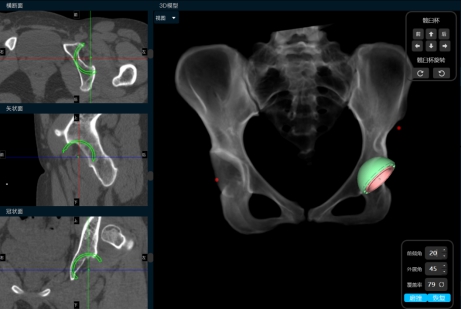

小张入院后,立即开始逐步进行相关检查,进行术前的准备。因为DDH的手术一般比较复杂,特别是这种脱位程度较高的患者,所以术前就需要更加精准的规划。对于小张的手术方法,耿硕制定了两套方案:一是如果原来真臼内及股骨头的软骨条件良好并且相匹配的话,那么可以尝试将股骨头放进髋臼里配合骨盆截骨重建髋关节;二是如果软骨条件不好或难以匹配,那么只能行全髋关节置换术。但是所有手术方案都会有一个挑战,就是如果在安装完髋臼杯及股骨假体后复位时把股骨下拉过多,可能会造成神经等软组织的牵拉伤并且因软组织张力过大可能造成假体松动,为了避免这种情况可能需要行股骨截骨减张,这样一期便不能恢复双下肢等长,需二期行骨延长术恢复下肢等长。在术前,为了适应软组织的张力状态及验证复位可能性,小张入院后即进行了患肢的牵引处置。为了精准的对手术做出规划,术前小张进行了下肢全长的三维CT扫描和模型重建,并且应用人工智能系统AI HIP对其进行术前手术方案的制定。人工智能能够利用患者的三维CT数据进行智能化识别解剖位点,匹配假体的大小及安放位置,通过对手术精准地预演,让外科医生在术前心中有数。通过人工智能系统的规划,计算出小张同学的双下肢腿长差和偏距差,计算出了旋转中心所需下移的距离和假体需要安放的位置等,髋关节置换方案为S-ROM假体系统,髋臼杯为PINNACLE 44号,内衬为BIOLOX28-44,因为患者比较年轻,所以选用了陶瓷对陶瓷的摩擦界面,能够实现更长的使用年限。根据术前规划数据,毕郑刚、耿硕团队提前准备了相应的假体和器械,为手术做了充分的准备。

(人工智能精准术前规划)